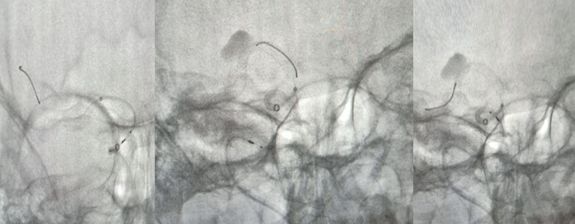

2、Pipeline密网支架释放过程,图像显示支架打开及贴壁良好(图二)。

治疗颅内动脉瘤新型密网支架,pipeline治疗椎动脉夹层动脉瘤

图二

3、术后支架显影(图三)。

图三